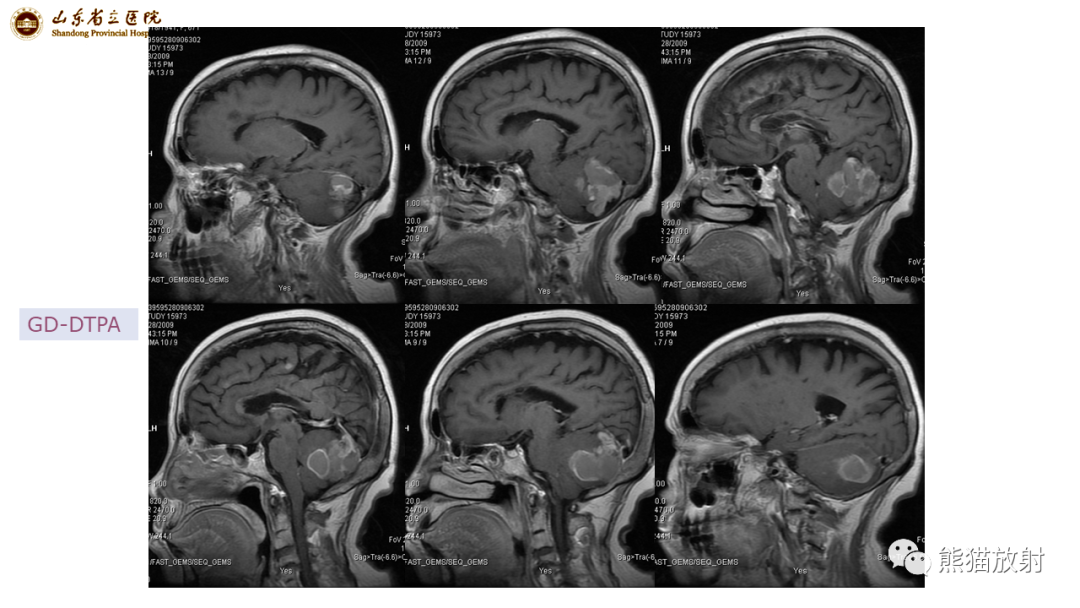

【病例】炎性肉芽肿并脓肿形成 & 成熟性囊性畸胎瘤-2